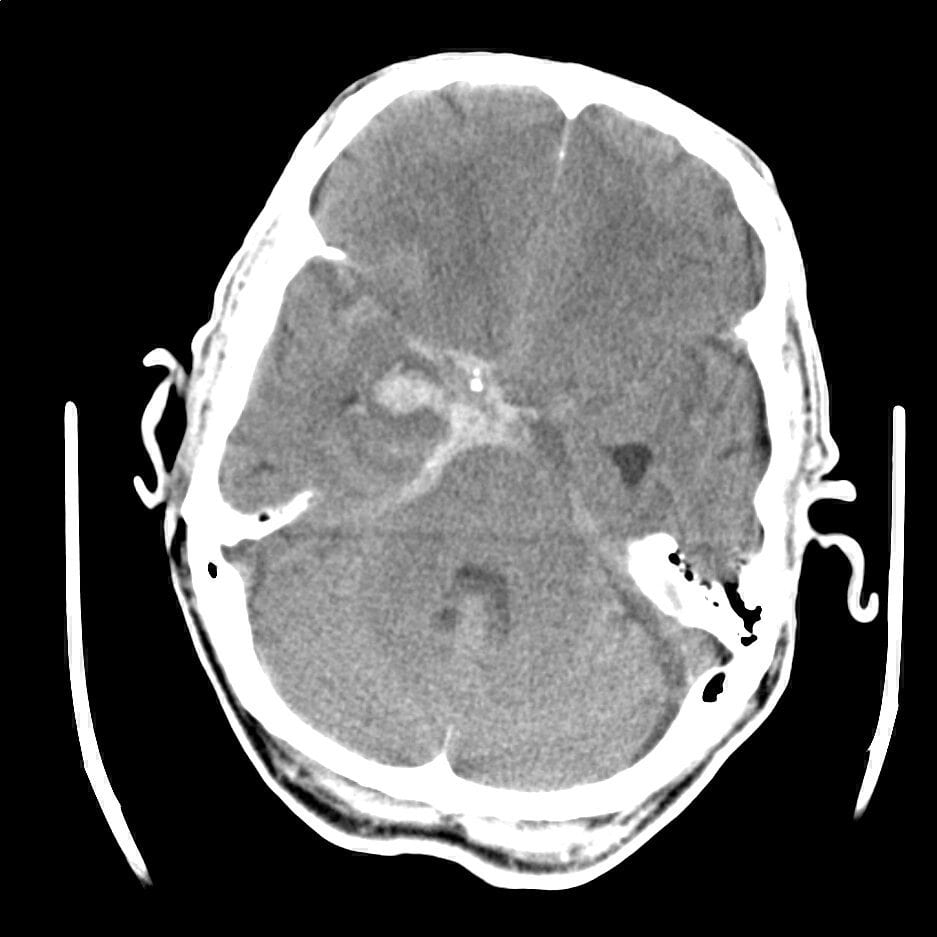

My very first case was doled to me first-thing on day one. A subarachnoid haemorrhage. This had progressed quickly to a decreased level of consciousness in the ED and so follow-up CT-A was done to observe the vessels. There were multiple areas suggestive of vasospasm, a common occurrence in these cases, and also a bad complication.

The solution with vasospasms is Nimodipine regular dosing, and pushing up their Mean Arterial Pressure(MAP) in 10mmHg steps until their level of consciousness improves. The theory is easy to understand. The vasospasms are blocking flow of blood into the brain, push up the blood pressure until there is evidence that the flow is sufficient and keep in there. Repeat CT-angiogram of the head to confirm resolution and we can begin to allow the blood pressure to fall back to physiological norms.